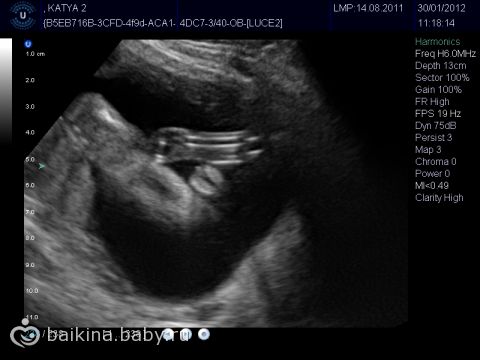

Это видео было сделано на сроке 14 нед. 3 дня. по УЗИ ещё + 2 дня. (14 нед. 5 д.)

Скрининг намечен на 21 число, но он будет в Ж/К, а узнать пол, это уже платно( Планирую через две недельки сходить в платную клинику, там и узнать кто у нас. Заодно и малыша покажут, видео сделают, фото) Была три дня назад на УЗИ с щитовидной (обход врачей), попросила глянуть пол, сказали малыш не удобно лежит, на 100% сказать не могут, может быть мальчик. На 14 неделе сказали может быть девочка. А вы как думаете?